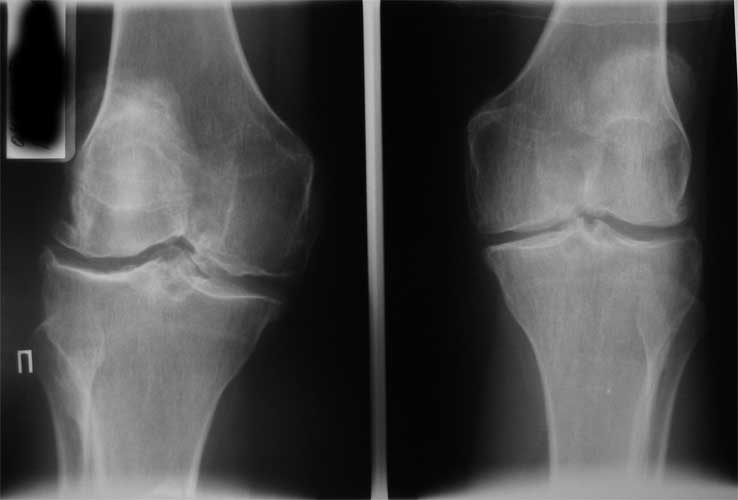

Уважаемые коллеги, пациентка 45 лет около 9 мес назад была прооперирована по поводу правостороннего коксартроза э/п LCS Complete RP.

послеоперационный период без особенностей, объем движений в 6 мес с/р - 110/0/0. Через 9 мес после операции возник напряженный гемартроз (без травмы, перегрузок), получено до 190 мл свежей крови, далее фиксация в ортезе, повторные пункции. через 2 нед выписана из стационара без признаков гемартроза. Через 2 нед аналогичная ситуация. Вопросы :причина? как лечить?